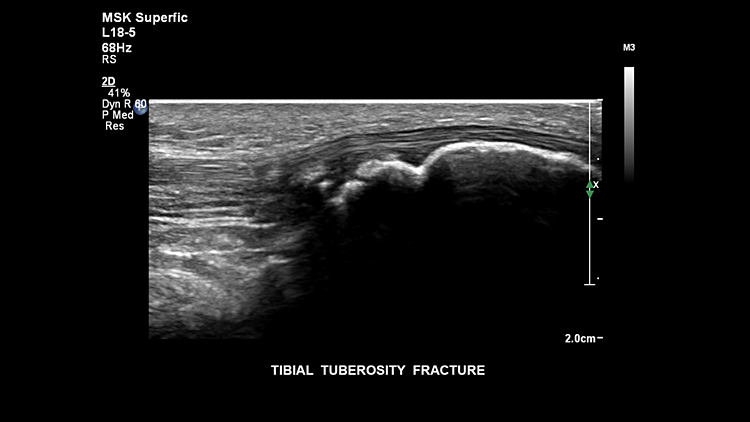

Перелом большеберцовой кости, L18-5